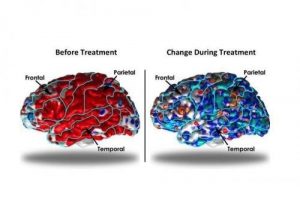

تصاویر اسکن شده از مغز بیمار افسرده ی مزمن ، قبل از درمان و حین درمان با rTMS

- شکل چپ، قبل از درمان می باشد .بیمار افسرده ، قشر ضخیم تری در لوب های فرونتال ، تمپورال و پاریتال مغز داشت .(رنگ قرمز)

- شکل راست، بعد از 10 هفته درمان این مناطق(رنگ آبی) دیگر از نظر ضخامت تفاوت ندارند .